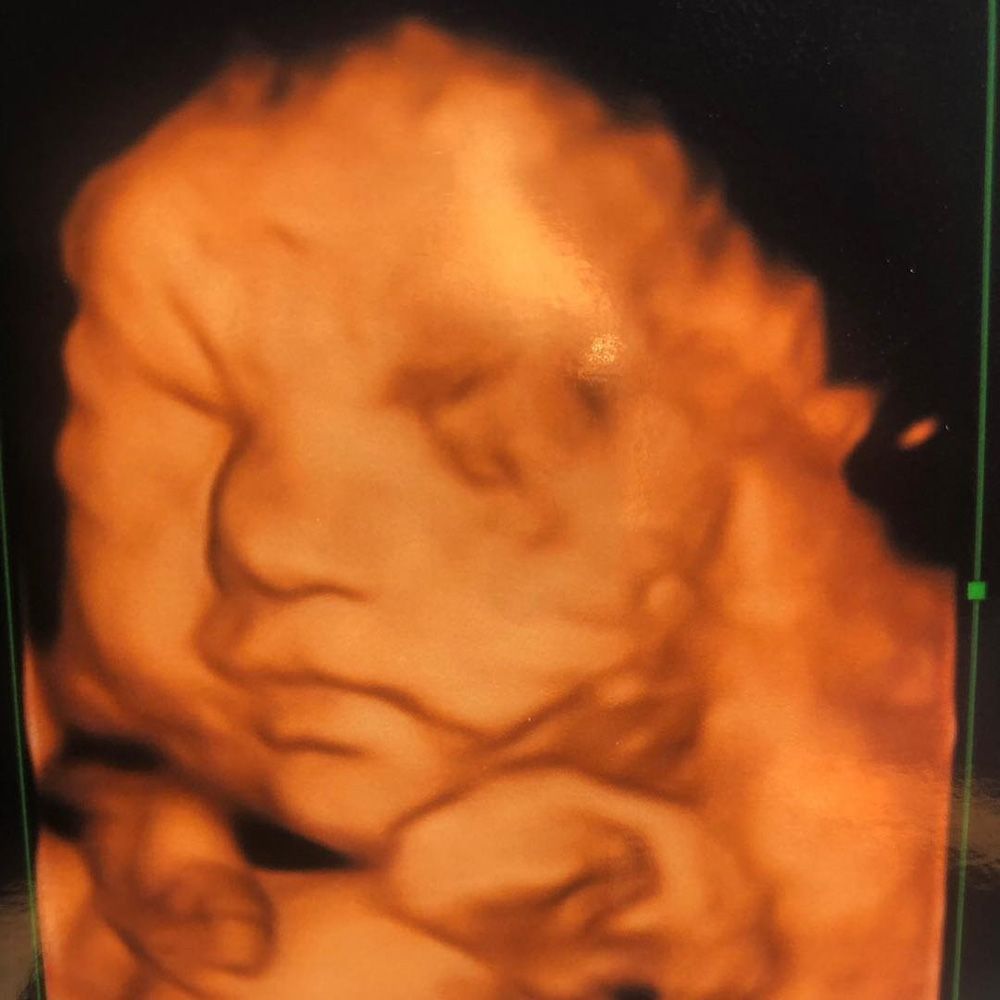

“I was asking the doctors if it could be something like measles, but they warned me to prepare for something bad like cancer. It was so frightening to keep hearing that word," she continued. “It's impossible to know before babies are born whether they will have this mark. We had a 4D scan, which showed that she had a lot of hair, but nothing to show she had a birthmark."